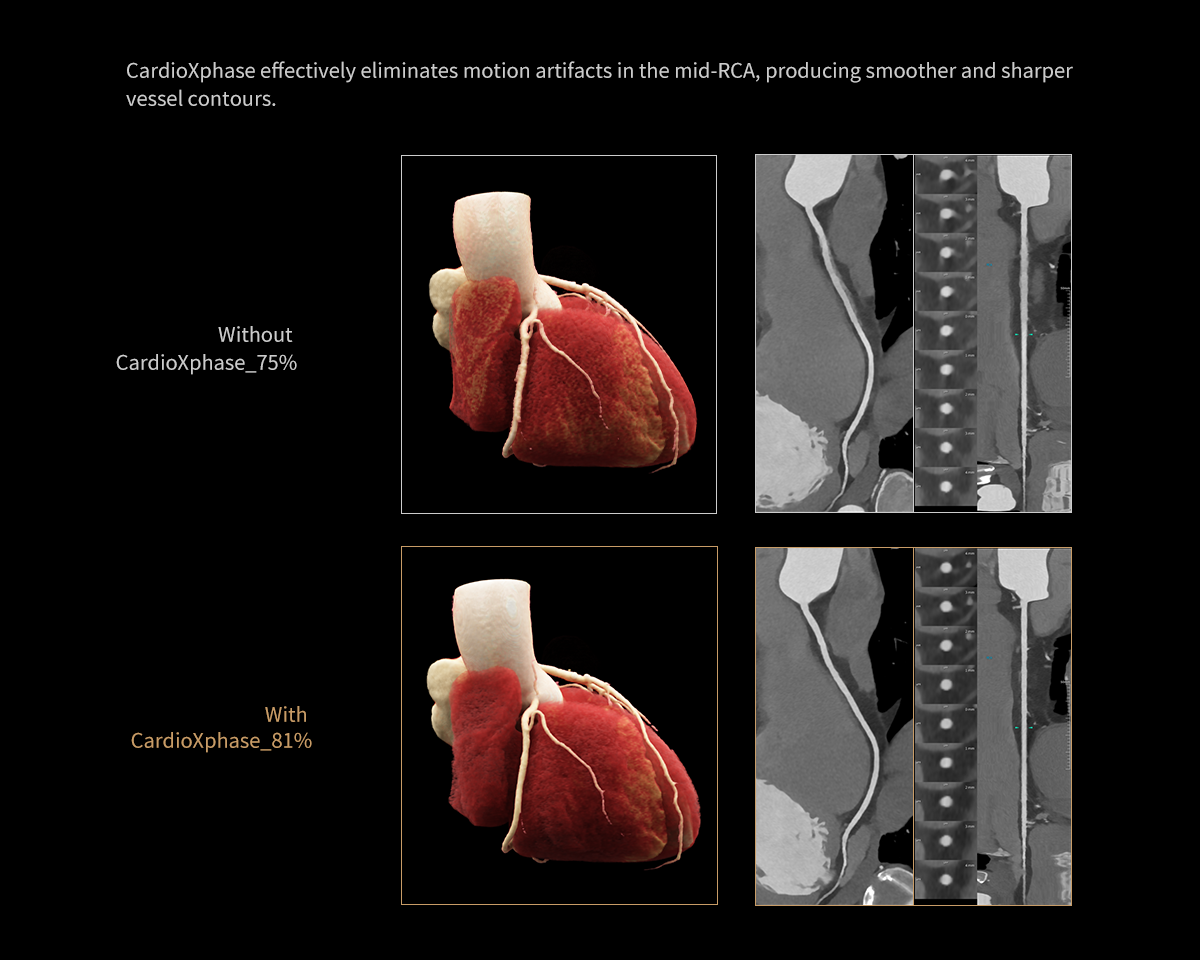

- CardioXphase: Finding the Optimal Phase for Coronary Arteries, Rather Than the Heart